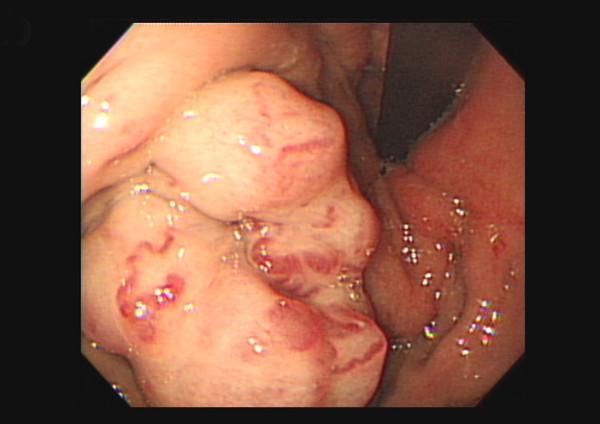

Primary splenic diffuse large B-cell lymphoma (DLBCL) is a rare clinical condition, which is generally treated by six to eight cycles of chemotherapy involving a combination of rituximab and the cyclophosphamide, adriamycin, vincristine, and prednisolone (CHOP) regimen. However, the treatment for chemorefractory primary splenic DLBCL remains controversial. Therapeutic splenic irradiation (SI) might be a reasonable and possibly the only treatment option with curative intention for patients with chemorefractory primary splenic DLBCL. However, the efficacy and safety of therapeutic SI are unclear. Herein, we present the case of a primary splenic DLBCL patient who was refractory to multiple chemotherapy regimens but achieved complete remission after administration of therapeutic SI. However, his condition was complicated with severe gastric variceal bleeding due to splenic venous thrombosis, which was successfully treated via splenectomy and short gastric vein ligation. On the basis of our findings, we concluded that the splenic venous thrombosis-induced gastric variceal bleeding was a rare but life-threatening adverse effect of the therapeutic SI administered for primary splenic DLBCL. Surgical intervention involving splenectomy and short gastric vein ligation is mandatory and should be performed as soon as possible for such patients.

原发性脾脏弥漫性大 B 细胞淋巴瘤(DLBCL)是一种罕见的临床病症,通常采用六到八个周期的化疗来治疗,其中包括利妥昔单抗和环磷酰胺、阿霉素、长春新碱和泼尼松(CHOP)方案的组合。然而,对于化疗耐药的原发性脾脏 DLBCL 的治疗仍然存在争议。治疗性脾照射(SI)可能是一种合理的、可能是唯一具有治愈意图的治疗选择,适用于化疗耐药的原发性脾脏 DLBCL 患者。然而,治疗性 SI 的疗效和安全性尚不清楚。在此,我们报告了一例原发性脾脏 DLBCL 患者的病例,该患者对多种化疗方案均耐药,但接受治疗性 SI 后达到完全缓解。然而,他的病情因脾静脉血栓形成而并发严重胃静脉曲张出血,通过脾切除术和胃短静脉结扎术成功治疗。基于我们的发现,我们得出结论,脾静脉血栓形成引起的胃静脉曲张出血是治疗原发性脾脏 DLBCL 时 SI 治疗罕见但危及生命的不良反应。对于此类患者,强制性的手术干预包括脾切除术和胃短静脉结扎术,并且应尽快进行。